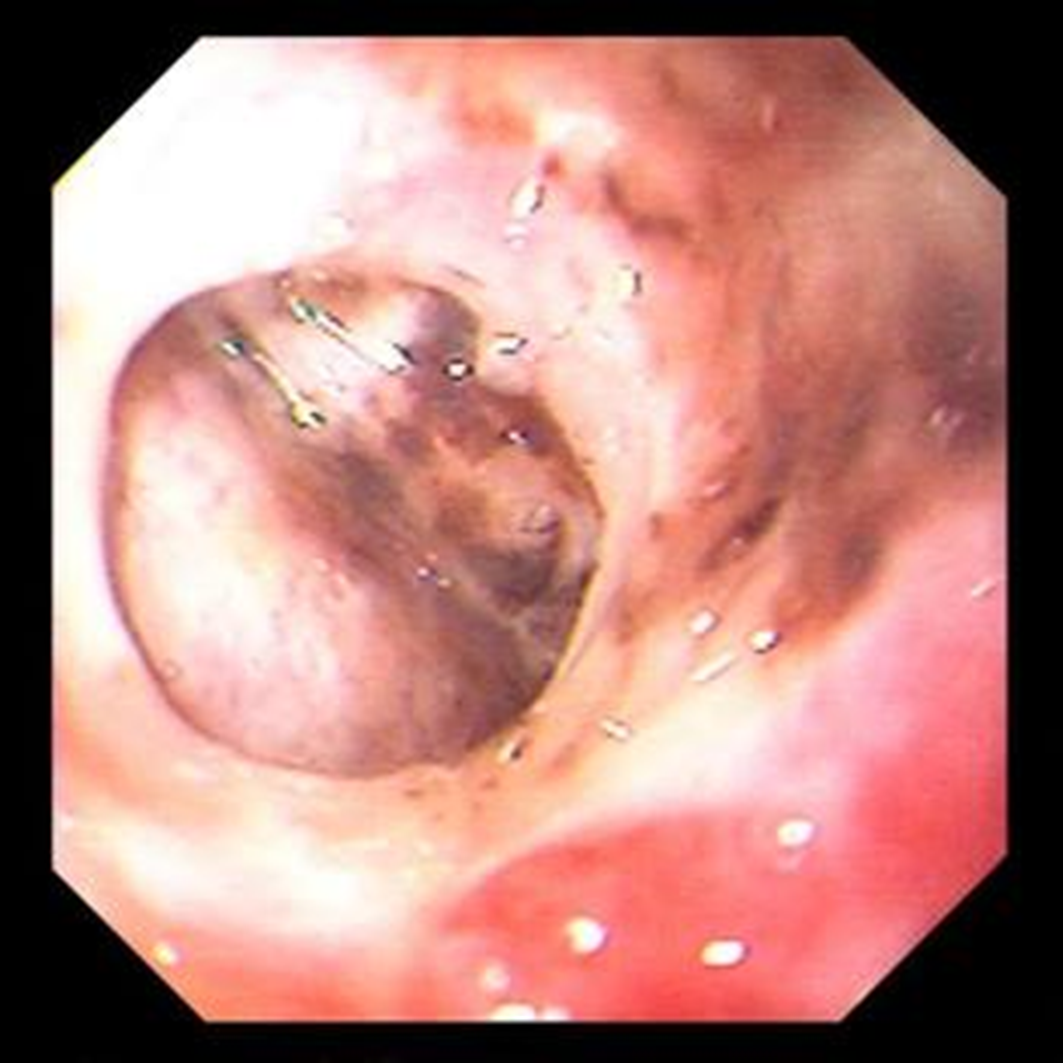

Xác định chẩn đoán khi Xquang hoặc CT bụng có hình ảnh khí dưới cơ hoành (liềm hơi) hoặc khí trong phúc mạc. Xquang ngực và bụng thẳng thường được chỉ định hơn. Trường quan sát nhạy nhất là Xquang ngực nghiêng. Bệnh nhân nặng có thể không thể ngồi thẳng nên chụp X quang bụng tư thế nằm nghiêng. Không thấy khí tự do cũng không loại trừ chẩn đoán.

Khí tự do

image 3